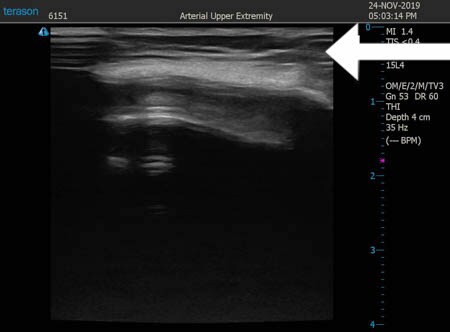

いつものように3Dタッチビュー(超音波)で

皮下脂肪層を評価してみましょう。

右ふくらはぎ